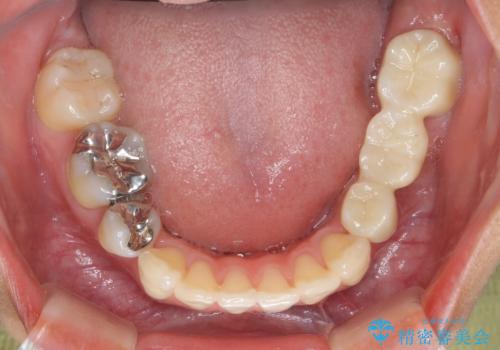

- 左下の銀歯の状態が悪く抜歯してブリッジにした患者様です。

抜歯してからブリッジの仮歯をすぐ入れるため、歯がない期間はほとんどありません。

- 36.3万円 (ジルコニアクラウン 10万円×3、仮歯1万円×3)費用は治療当時の料金となります

途中全体矯正をはさみ、根の向きが並行になった状態でブリッジを入れることができました。